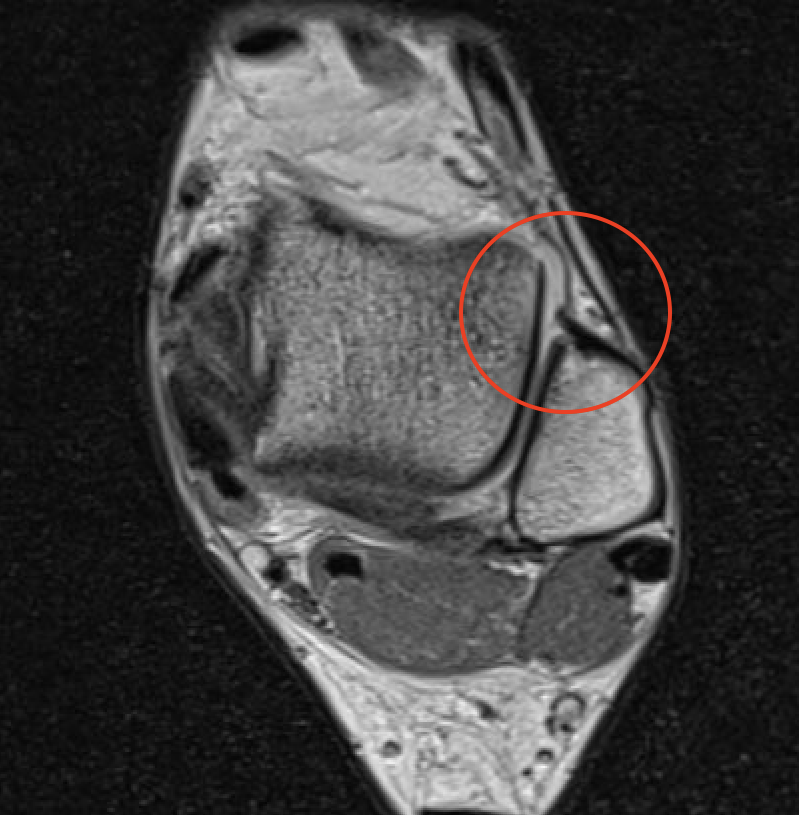

MRI

ATFL tear